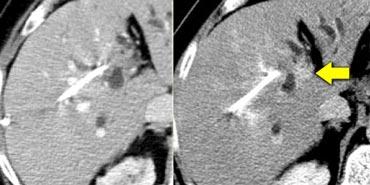

Ung thư biểu mô đường mật kích thước nhỏ không quan sát thấy trong thì tĩnh mạch cửa (trái), nhưng hiện ra là tổn thương tương đối tăng tỷ trọng trong thì muộn (phải).

Tổn thương tương đối tăng tỷ trọng trong thì muộn

Mô xơ có cấu trúc chặt chẽ và dày đặc rất chậm cho phép iod hoặc gadolinium thấm vào.

Tuy nhiên, một khi thuốc cản quang đã vào, nó cũng thải ra rất chậm trong thì cân bằng.

Vì vậy, khi nhu mô gan bình thường thải thuốc, các thành phần xơ của khối u sẽ trông sáng hơn so với nhu mô gan xung quanh.

Ung thư biểu mô đường mật có thể có mô đệm xơ và trong thì muộn đây có thể là thời điểm duy nhất quan sát thấy khối u (hình).

Tổn thương tương đối giảm tỷ trọng trong thì muộn

Hình bên trái minh họa tầm quan trọng của thì muộn ở bệnh nhân xơ gan có HCC.

Lưu ý rằng không thấy khối u trên hình chụp không tiêm thuốc và cũng không thấy trong thì tĩnh mạch cửa. Đây thường là trường hợp hay gặp và cho thấy tầm quan trọng của thì động mạch.

Vấn đề đặt ra là đối với các tổn thương ngấm thuốc nhỏ trên nền gan xơ, liệu đó là tổn thương lành tính như nốt tái tạo hay HCC.

Trong thì muộn, chúng ta thấy khối u thải thuốc nhiều hơn so với nhu mô gan xung quanh.

Các tổn thương lành tính thường không có kiểu thải thuốc này.

Mặc dù u gan nguyên phát thường tăng sinh mạch, vẫn có ngoại lệ. 10% HCC là giảm sinh mạch. Ung thư biểu mô đường mật (cholangiocarcinoma) giảm sinh mạch nhưng có thể ngấm thuốc muộn (hình).

Bên trái là một khối giảm sinh mạch với ngấm thuốc không đều trong thì động mạch muộn và thì tĩnh mạch cửa muộn. Đây là dấu hiệu của ác tính.

Trên các hình ảnh thì muộn, quan sát thấy một cấu trúc tương đối tăng tỷ trọng ở trung tâm, thải thuốc chậm hơn so với nhu mô gan bình thường.

Điều này cho thấy khối u này chủ yếu được cấu thành bởi mô xơ.

Mô xơ cũng gây co rút bao gan.

Các đặc điểm hình ảnh này rất gợi ý chẩn đoán ung thư biểu mô đường mật.